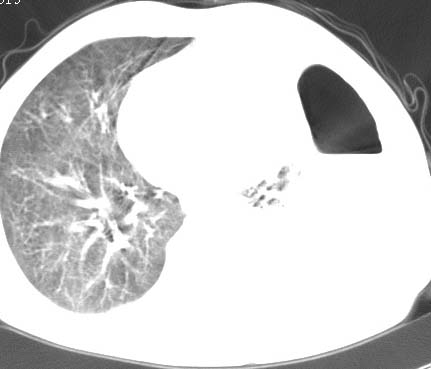

标题: CT10145:男性,30岁,活动后气促2月余.隔疝伴胸腔积液.右上肺结 [打印本页]

男性 病人 30岁,活动后气促2月余.隔疝伴胸腔积液.右上肺结核!

双肺上结核;膈肌裂孔疝。

左侧胸腔积液,并胸腔内见多个含液 气组织,并相互重叠。影像特征很特殊,应该是“膈疝”。支持!

左侧膈疝,及左侧胸水,双上肺结核。

支持!左侧膈疝,左侧胸水,双上肺结核。